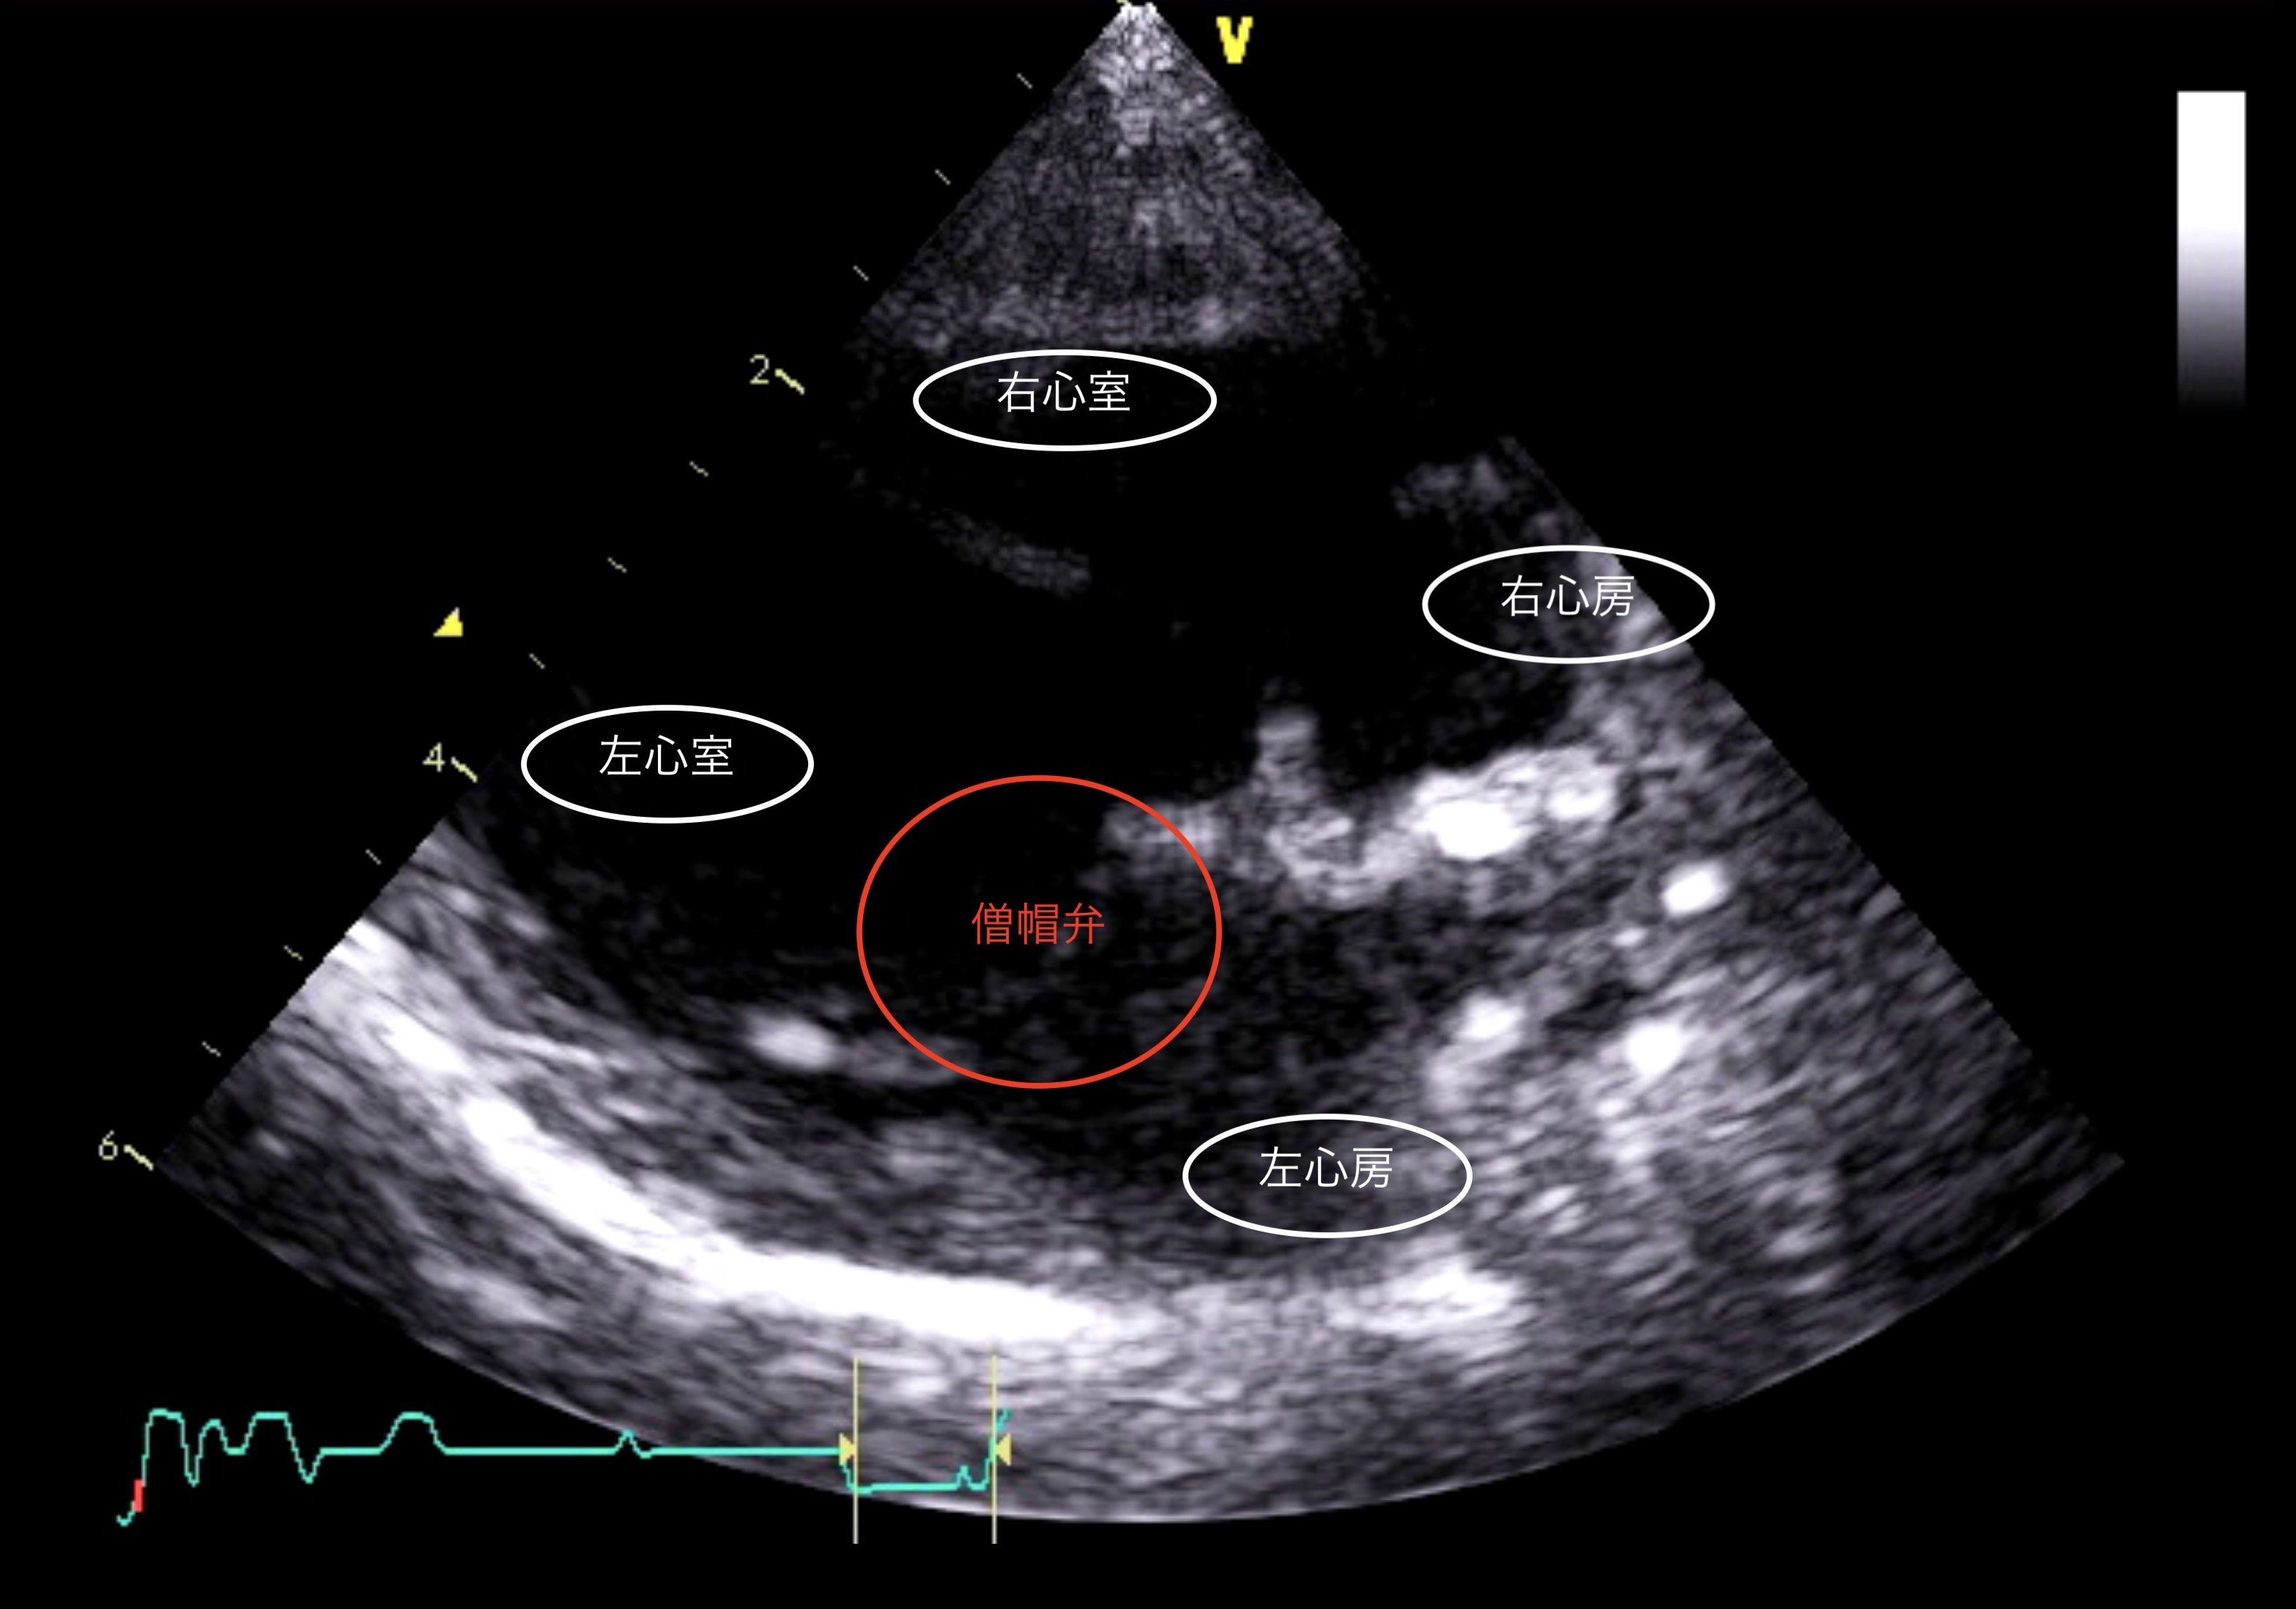

心臓の左側の部屋(左心房/左心室)を仕切る弁(僧帽弁)の閉鎖が不完全なことが原因で、血液の逆流が起こり症状を起こします。

超音波検査では、僧帽弁閉鎖不全による血液の逆流が認められ、内服を開始しました。